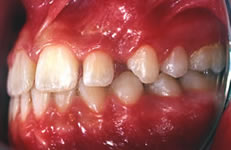

Terapia ortodontica - Prima (FIG 3)

La paziente S.A., di anni 12, presenta morso crociato posteriore monolaterale (fig. 1) dovuto a deviazione della mandibola verso destra in fase chiusura , pertanto le linee interincisive risultano non coincidenti (fig. 2). Si rileva inoltre l’assenza in arcata del canino superiore di sinistra ( incluso) e carenza di spazio per lo stesso (fig. 3 e 4).